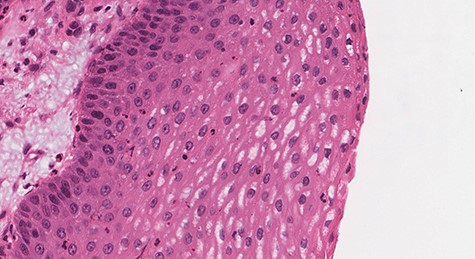

Histologic sections show an endophytic (inverted) pattern that grows downward into the underlying stroma (Fig. 4). The epithelium consists of hyperplastic squamous epithelium (Fig. 5) and ciliated columnar cells admixed with scattered mucocyets (goblet cells) (Fig. 6). The cells have a bland appearance and uniform small nuclei. No cytologic atypia, increased mitotic activity or necrosis seen. Mixed inflammatory cells are dispersed within the epithelium and stroma.